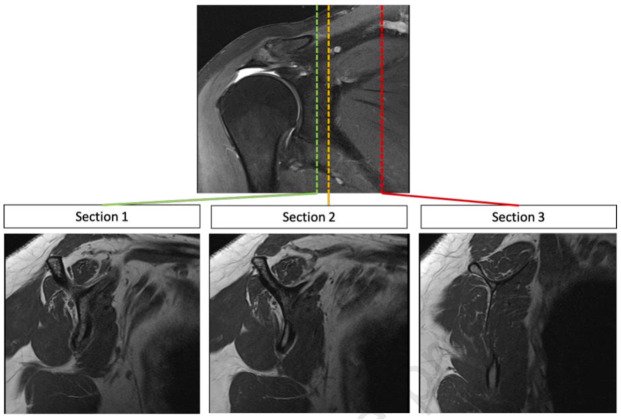

Our recently published study, “Automated classification of fatty infiltration of rotator cuff muscles on MRI using deep feature fusion and machine learning,” continues to gain momentum. With accuracy of over 91% and performance consistent with expert-level classifications, this work highlights the potential of AI to improve consistency and efficiency in preoperative planning.